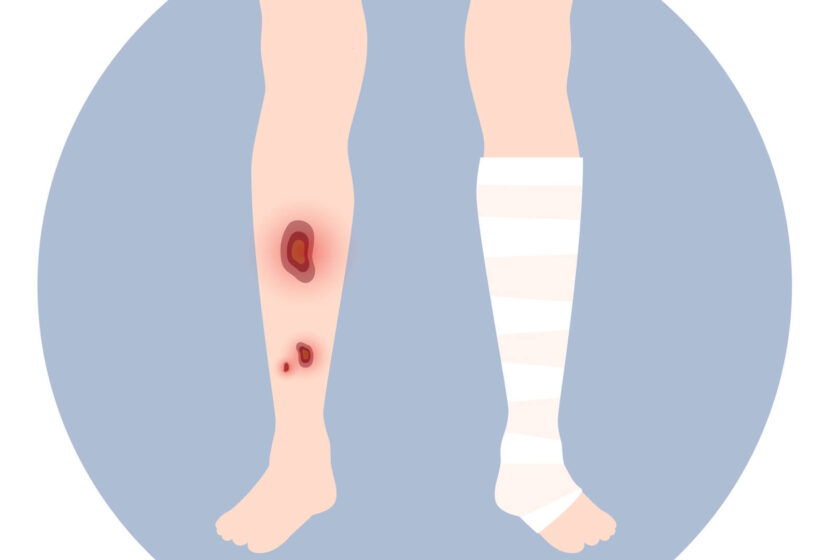

Venous ulcers often develop on the inside of the leg just above the ankle. Typically associated with stasis dermatitis and venous insufficiency, these skin sores can cause discomfort and swelling in the affected leg. The surrounding area might exhibit a burning sensation, which often signifies a potential venous ulcer. Moreover, if the ulcer leads to tissue infection, it can complicate the condition further.

Several distinctive signs and symptoms can point to the presence of a venous ulcer:

- A feeling of heaviness and cramping in the leg. This can be associated with discomfort and pain in the affected area.

- The ulcer typically appears shallow with a red base, often coated with yellow tissue, a clear sign of an inflamed wound.

- The borders of the sore are typically irregular, further hinting at the presence of a venous ulcer.

- The skin around the ulcer may exhibit a shiny and tight texture, often feeling warm or hot to the touch.

- In the event of an infection, the ulcer may produce a foul smell and drain pus, indicating a serious complication that needs immediate medical attention.

Interestingly, the ulcer itself usually doesn’t cause significant pain. If a patient experiences pain, it’s likely due to infection or swelling (edema) in the surrounding area. In more severe cases, the entire leg can swell, hardening the skin, a sign of blood pooling, and taking on a reddish-brown appearance.

One common approach to reducing the swelling associated with venous ulcers involves the use of compression bandages or stockings. This method helps to enhance blood circulation in the legs, thereby boosting the body’s healing capacity. The type of bandage required varies from patient to patient. Some might need to wear compression bandages continuously, replaced by a doctor every few days. Others may require wearing them only during the daytime, enabling the patient to apply and remove them independently. For wearing stockings, you may see our you tube video.